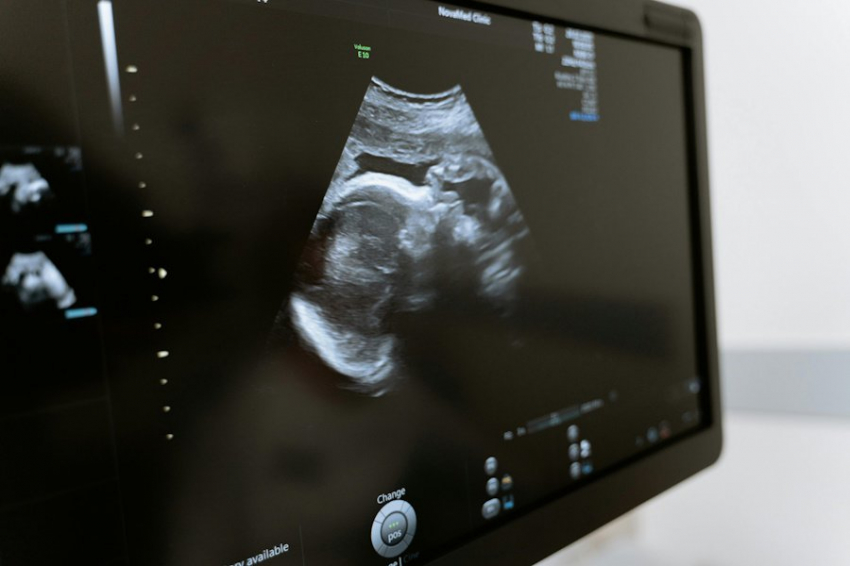

COVID-19 у матери в период беременности может грозить риском аутизма у ребенка

Ученые Калифорнийского университета обнаружили, что у 11% детей, подвергшихся воздействию COVID-19 в утробе матери, диагностировано расстройство аутистического спектра (РАС). Об этом сообщило издание Bloomberg, ссылаясь на результаты исследования. Обычно распространенность этого расстройства среди детей в таком возрасте составляет 1–2%.